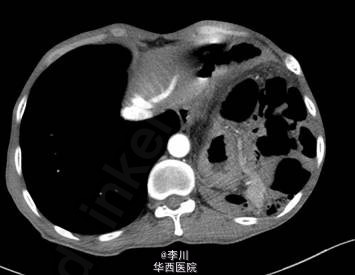

在全麻下经左胸膈疝修补、胸膜粘连烙断、胸腔闭式引流术。术中发现:左膈肌外侧缺损约15cm×12cm大小,腹腔内网膜、胃及横结肠等组织疝入胸腔。网膜、胃、结肠组织与膈肌、胸壁片状粘连。左侧肺与胸壁广泛粘连。术后予抗炎、化痰、对症等治疗后好转。

膈疝分为创伤性膈疝与非创伤性膈疝,创伤性膈疝是由于外伤致膈疝破裂,腹腔脏器病入胸腔所致,是胸外科急重症,常合并胸腹腔脏器损伤或严重的呼吸循环障碍。膈肌损伤无论大小均不能自愈,所以膈肌破裂一旦诊断明确,在治疗危及生命的创伤及休克的前提下,只要能耐受手术均应及时手术治疗。手术路径视患者胸腹部伤情而定,按照先重后轻的原则,首先处理致命伤,术式要简单有效。